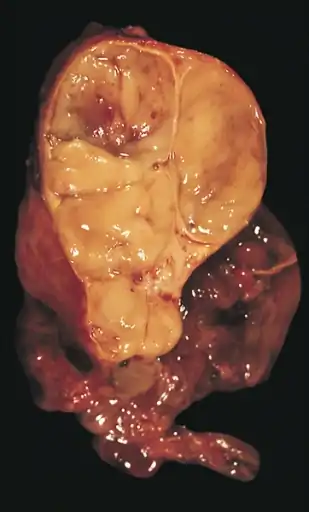

Un timoma encapsulado (de tipo linfocítico y epitelial combinado). | ||

An encapsulated cystic thymoma.

An encapsulated cystic thymoma. A locally invasive circumscribed thymoma (mixed lymphocytic and epithelial, mixed polygonal and spindle).